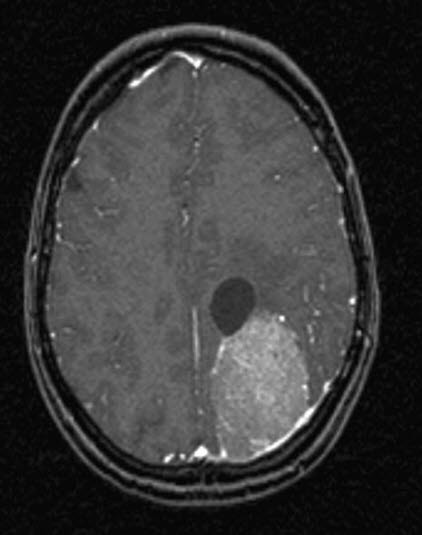

Meningeom med cyste, aksialt snitt

Gjengitt med tillatelse av Radiologisk avdeling, Universitetssykehuset Nord-Norge